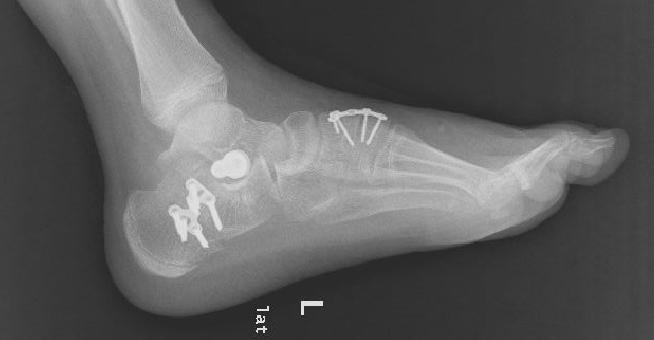

上图为患者扁平足术后影像资料

根据病情,小儿骨科积极邀请昆明医科大学第二附属医院骨科足踝专家进行会诊及手术指导。经医院小儿骨科和昆明医科大学第二附属医院骨科足踝专家的配合,对该复杂僵硬性扁平足患者进行了左侧扁平足跟骨内移截骨钢板固定,距下关控制动器置入,副舟骨切除,胫后肌腱止点重建术,腓长肌松解,内侧楔骨截骨植骨钢板固定,取同侧髂骨植骨术等多处复杂性手术治疗,手术历经2小时,圆满顺利完成。